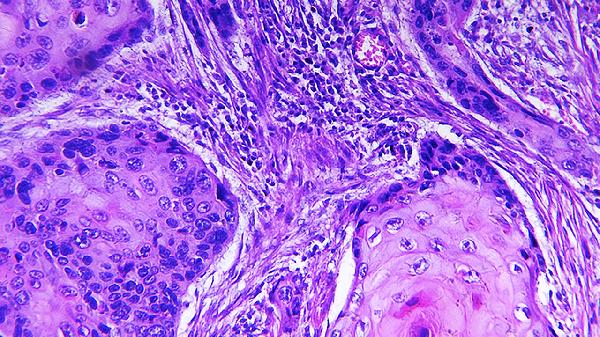

2、核磁共振成像

采用头颅或脊髓MRI平扫加增强扫描,可清晰显示脑白质、视神经等部位的脱髓鞘病灶。多发性硬化患者的病灶多呈卵圆形,分布于侧脑室周围、胼胝体等区域。MRI弥散张量成像还能评估神经纤维束完整性,检查无辐射但需去除体内金属异物。